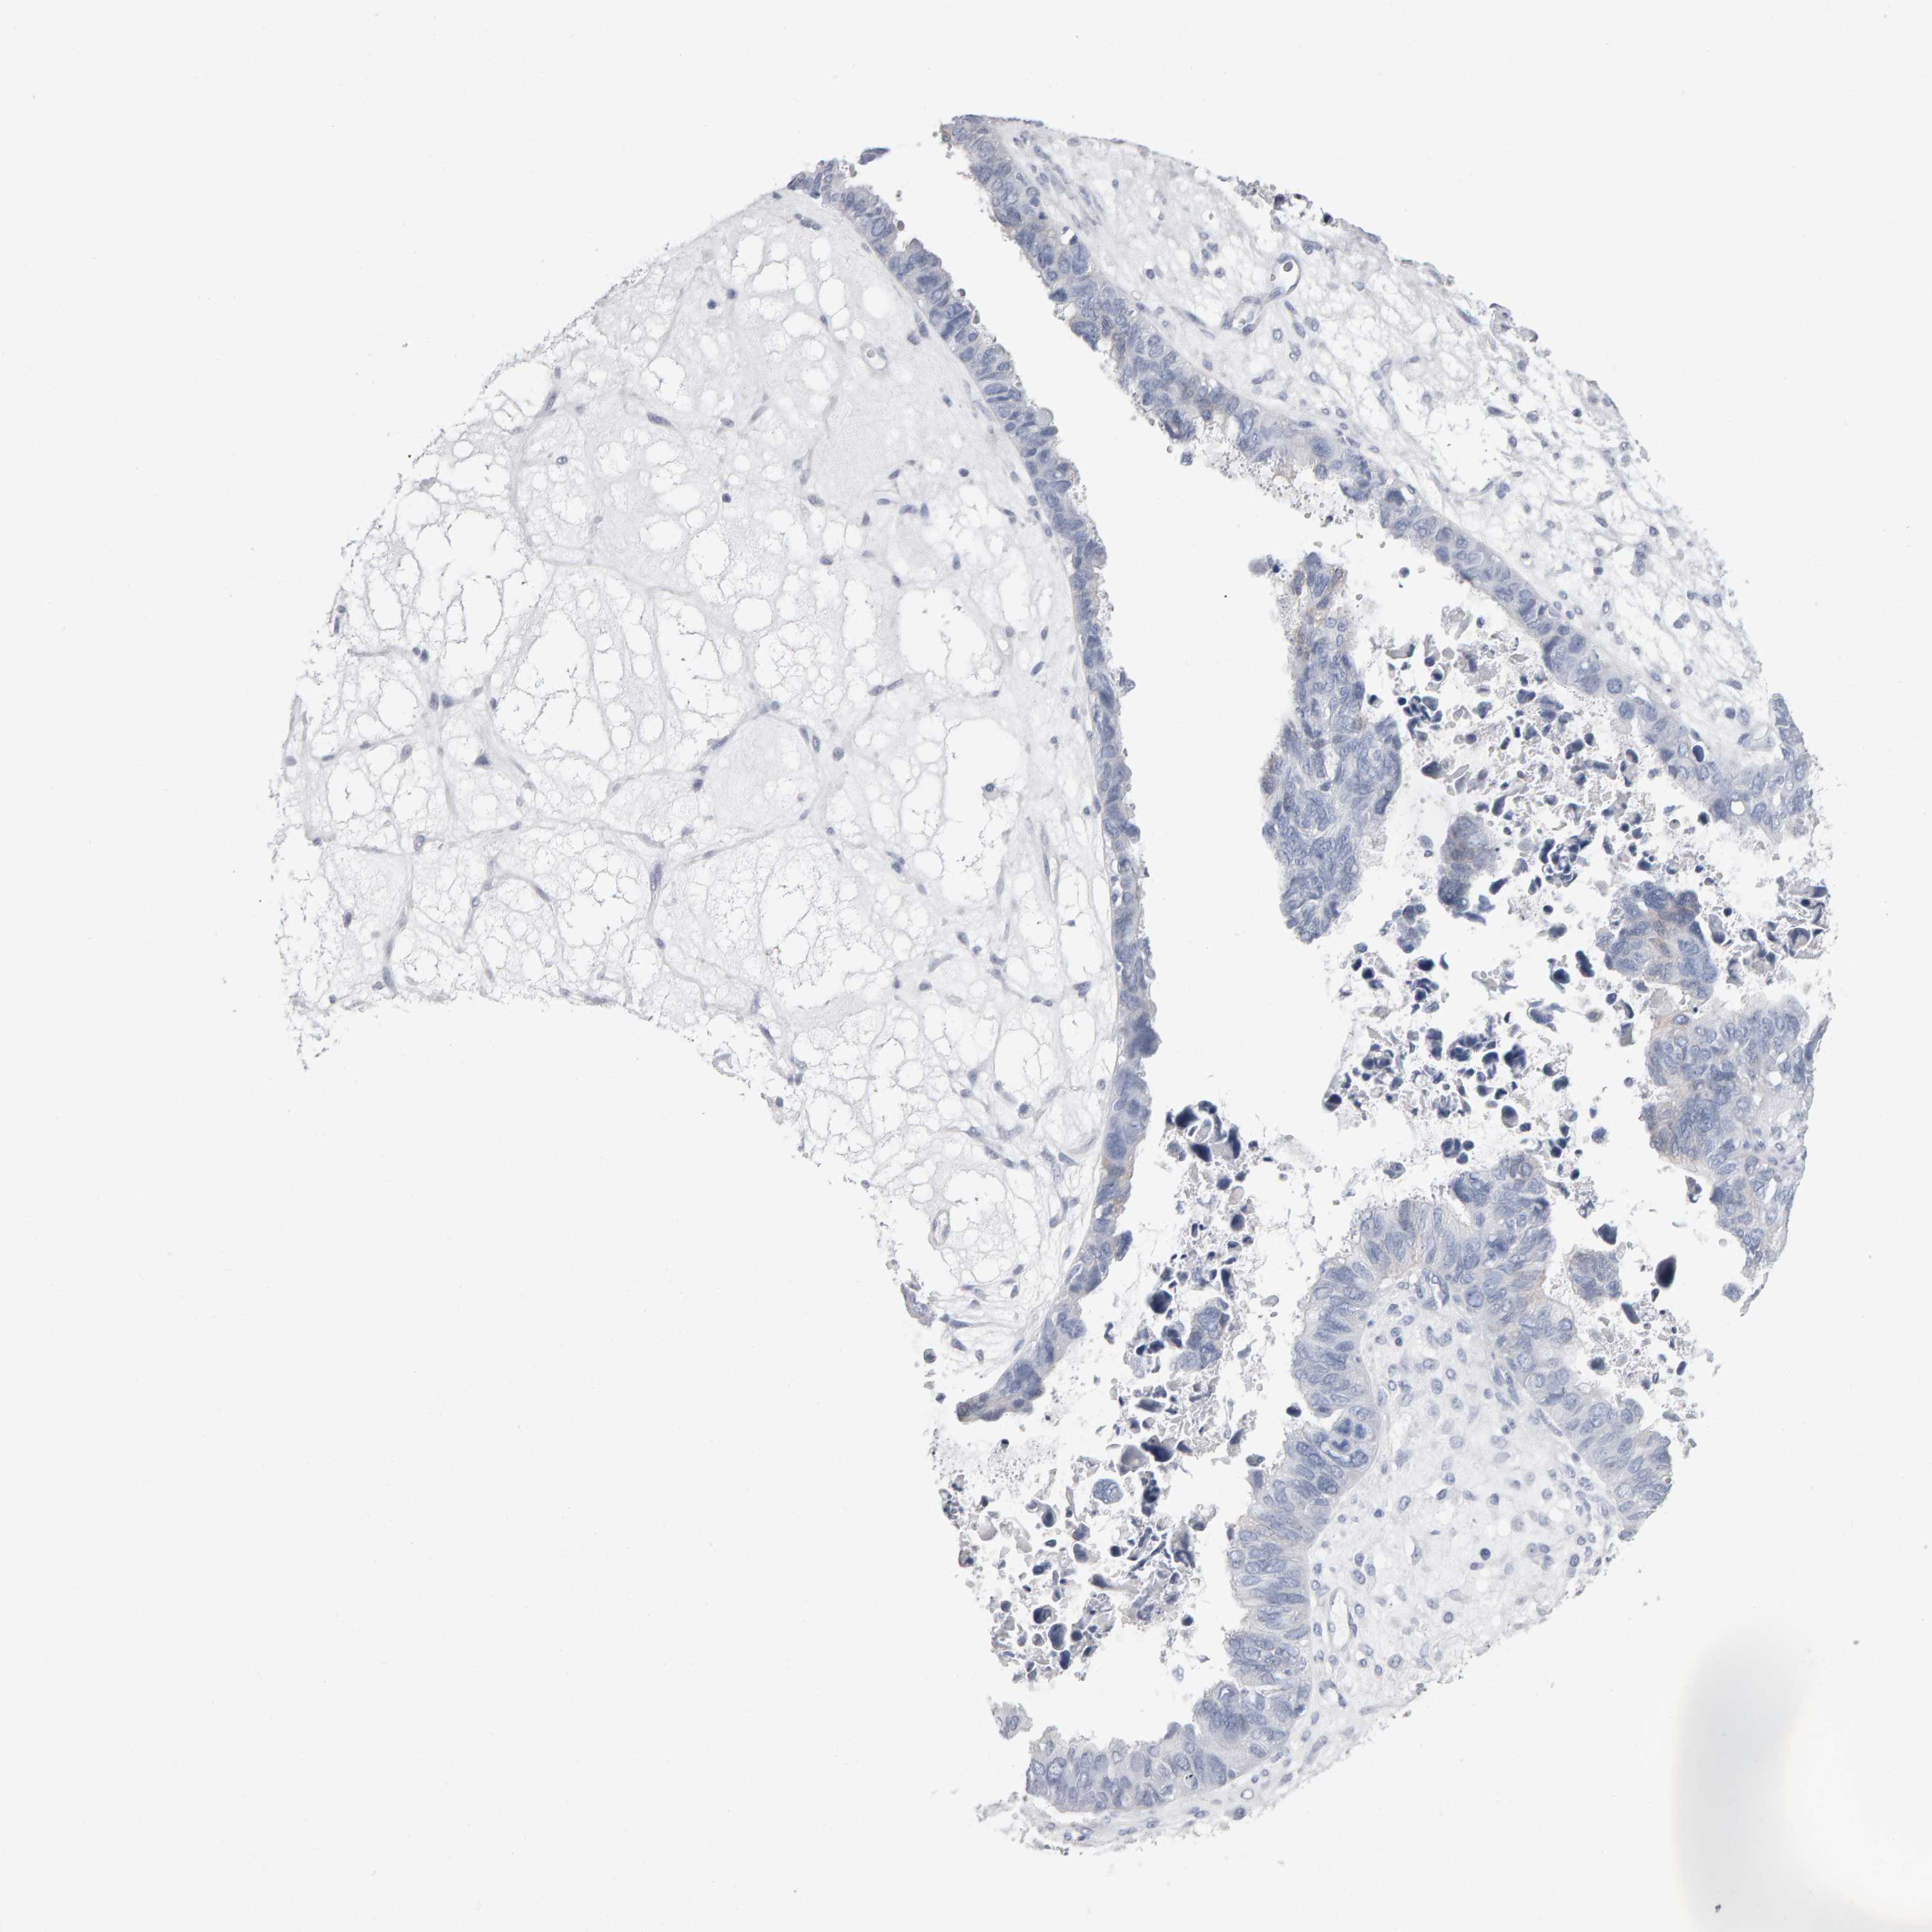

OVARIAN CANCER - Protein expressioni

A mouse-over function shows sample information and annotation data. Click on an image to view it in a full screen mode. Samples can be filtered based on level of antibody staining by selecting one or several of the following categories: high, medium, low and not detected. The assay and annotation is described here.

Note that samples used for immunohistochemistry by the Human Protein Atlas do not correspond to samples in the TCGA dataset.

Antibody stainingi

Antibody staining in the annotated cell types in the current human tissue is reported as not detected, low, medium, or high, based on conventional immunohistochemistry profiling in selected tissues. This score is based on the combination of the staining intensity and fraction of stained cells.

Each image is clickable and will lead to virtual microscopy that enables deeper exploration of all samples and also displays staining intensity scores, fraction scores and subcellular localization as well as patient and tissue information for each sample.

Antibody HPA023676

Staining

High

Medium

Low

Not detected

Intensity

Strong

Moderate

Weak

Negative

Quantity

>75%

75%-25%

<25%

None

Location

Nuclear

Cytoplasmic/membranous

Cytoplasmic/membranous,nuclear

Cystadenocarcinoma, serous, NOS

Carcinoma, endometroid

Cystadenocarcinoma, mucinous, NOS

Carcinoma, NOS